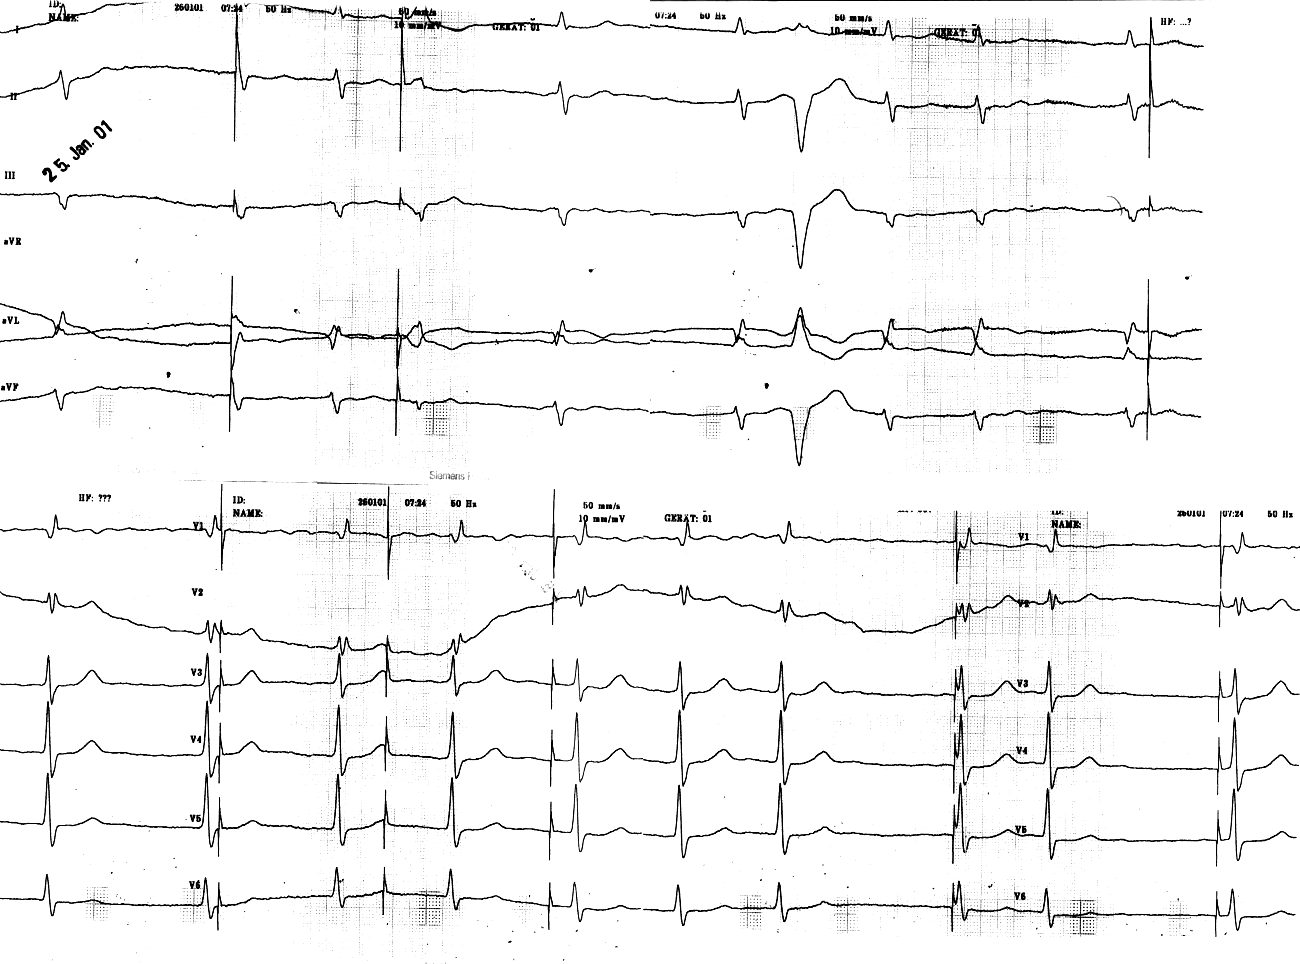

75j. Pat., Z.n. Schrittmacher-Implantation am Vortag

Auswertung

- absolute Arrhythmie bei Vorhofflimmern

(HF 70-90/min)

- überdrehter Linkstyp

- Zeiten: QRS 0,10s

QT 0,35s (QTc 0,38s)

Formveränderungen + Rhythmus:

- rsR'-Konfiguration in V1/2, tiefe

S-Zacken bis V6

- Schrittmacher-Stimulationen ohne

Korrelation zum QRS-Komplex (offensichtlich keine Auslösung von

Kammeraktionen durch den Schrittmacher-Impuls)

- 1 früheinfallende, "interponierte"

VES (keine kompensatorische Pause)

Diagnose

1. normofrequentes Vorhofflimmern

mit absoluter Arrhythmie

2. inkompletter Rechtsschenkelblock

3. linksanteriorer Hemiblock

4. SM-Sondendislokation mit Malsensing

und unkontrollierten Stimulationen (u.a. in vulnerable Phase)

5. V.a. R-auf-T-Phänomen